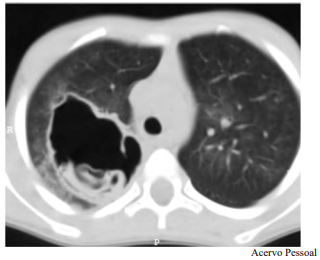

Determinado paciente de 49 anos de idade, morador em zona rural, iniciou com quadro de tosse importante, com piora progressiva, de início há dois meses, associada a alguns episódios de vômica. Refere febrículas na última semana. O paciente é tabagista leve, trabalha com criação de ovelhas e mora em casa com cachorros e gatos. Nega viagens internacionais recentes. Não foi encontrada nenhuma alteração no exame físico. Verificaram-se FC = 80 bpm, FR = 20 irpm e SatO2 = 99% em ar ambiente. A tomografia de tórax apresenta uma lesão cística de paredes espessas e conteúdo heterogêneo em seu interior, conforme representado na imagem a seguir.